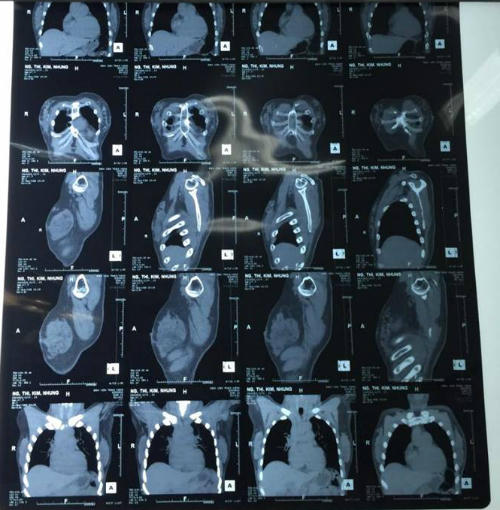

Bác sĩ Phạm Trịnh Quốc Khanh, Trưởng Khoa Phỏng Tạo hình Thẩm mỹ Bệnh viện Trưng Vương cho biết bệnh nhân đến viện ngày 22/9, kết quả khám ghi nhận khối cứng chắc ở hai má. Vùng ngực có nhiều khối u chắc, kích thước đa dạng và rải rác khắp tuyến vú hai bên. CT Scan cho thấy nhiều nốt cản quang nằm rải rác ở mô mỡ và mô tuyến vú.

Kết quả CT Scan. |

Bệnh nhân được phẫu thuật cắt trọn mô tuyến vú hai bên vào ngày 23/9. Kết quả giải phẫu ghi nhận mô mỡ, mô tuyến vú hai bên có nhiều u silicon, nặng khoảng 500 g. Ngoài ra có vài u nhỏ kích thước khoảng 5 mm cứng chắc, màu đen xám hai bên vú. 3 ngày sau mổ, bệnh nhân hồi phục tốt, vết mổ khô và tái khám theo dõi định kỳ.